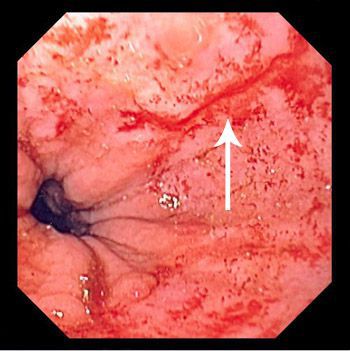

Violent coughing or retching can cause tears in the lower esophagus. These tears are known as Mallory Weiss tears. The tearing of lower esophagus may also occur secondary to hiatal hernia or any etiology causing rise in intrabdominal pressure. The signs and symptoms of Mallory Weiss tears are: - Bright red vomiting / vomit with coffee grounds - Black stools - Weakness - Dizziness - Dyspnea - Diarrhea Reference: https://www.hopkinsmedicine.org/health/conditions-and-diseases/malloryweiss-tear Image via: https://www.msdmanuals.com/professional/gastrointestinal-disorders/esophageal-and-swallowing-disorders/mallory-weiss-syndrome